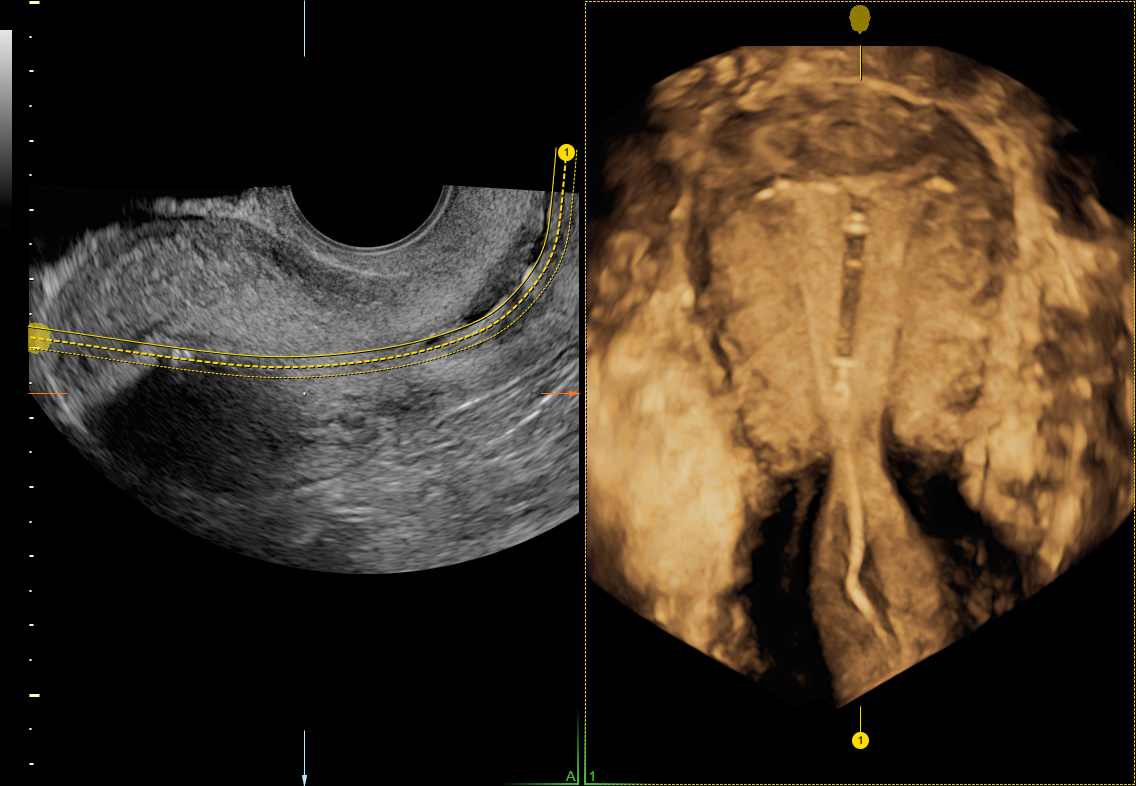

Ultrasound image of hormonal IUD. (A) 2D image; (B) 3D rendering, with Copper Iud Ultrasound Here we present two patients in whom a copper iud was found to have missing portions of copper wire upon removal of an otherwise intact. Because of this mechanism, copper iuds are. 2d sagittal (c) and transverse (d) sonograms show the bright echo of the copper iud with marked posterior shadowing. Both iuds have monofilament threads that. The copper iud. Copper Iud Ultrasound.